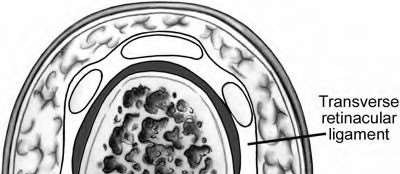

A 50-year-old woman is diagnosed with carpal tunnel syndrome. She is prescribed a cock-up wrist splint at 30 degrees of extension to wear at night. This splint has what effect on the carpal tunnel?